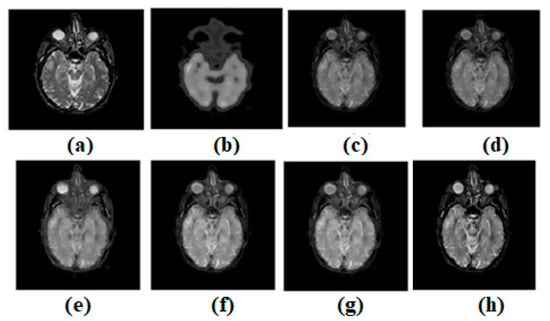

Figure 6.

(a) Source image: MR, (b) Source Image: PET, (c) Result of [44], (d) Result of [47], (e) Result of [48], (f) Result of [49], (g) Result of [51], (h) Result of [53].

Input source images are shown in Figure 6a,b. All images, for non-conventional methods [44,47,49,51,53], are fused with established structures. Figure 6c–g, respectively, expresses the results of [44,47,49,51,53]. In this regard, the results of ref. [53] seem better compared to other existing methods. The result of ref. [51] is also satisfactory. However, the results of methods refs. [44,47,49] are not satisfactory. Figure 6 shows that while the result of ref. [44] is passable, it fails to adequately preserve edges and textures. Nonetheless, disparities persist. The original texture has been preserved in a few regular places. However, in a field with so many variations, clarity is lacking. As can be seen in Figure 6, while the output of ref. [47] is serviceable, it falls short of expectations in terms of maintaining edges and textures. Contrasts are kept well and the texture has been well-preserved and is uniform in some areas. Unfortunately, the heterogeneous area is severely lacking in light. As can be seen in Figure 6, the outcome of ref. [49] is passable, but it fails to adequately preserve the image’s edges and textures. However, the contrasts in ref. [48] have been preserved well. Consistency may be found in some places, and the original texture has been preserved with meticulous attention to detail. These are not the only locations where the texture has changed. However, there is not enough illumination to properly study the region’s heterogeneity. Figure 6 shows that while ref. [51] produces a good image, it fails to meet expectations in terms of edge and texture preservation. There is a high level of talent involved in maintaining the texture while also achieving continuity in a number of key locations. As opposed to this, the area of varying luminosity is known as the “heterogeneous zone.” Figure 6 shows acceptable output from ref. [53], but note that it does not preserve the edges or textures. However, there are still clear delineations between the elements. In some areas, the surface’s uniformity and texture have been preserved. However, the brightness is very low in highly textured areas.